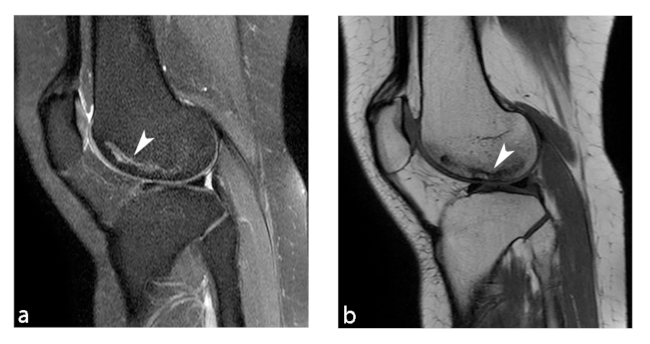

Los primeros estadios de la lesión se caracterizan por una fractura subcondral sin asociación de hallazgos osteonecróticos, reconocida en RM por una imagen lineal de baja señal ponderada en T1, subcortical, y edema periférico extenso mejor evidenciado en secuencias ponderadas en T2. Al avanzar su estadio, estas lesiones osteonecróticas muestran cambios distales por una cicatrización deficiente, lo que genera reacción y formación de cartílago con tejido fibroso indicativo de retraso o falta de unión.11

En RM en secuencia ponderada en T1, la intensidad de señal de la grasa de la médula ósea del cóndilo femoral afectado es reemplazada por un área con baja señal, asociada a una periferia de aún más baja señal (►Figs. 4 y 5).8 En la secuencia ponderada en T2 se visualiza lesión central hipointensa con área de señal alta periférica en relación al patrón de edema de la médula ósea (►Fig. 6).11